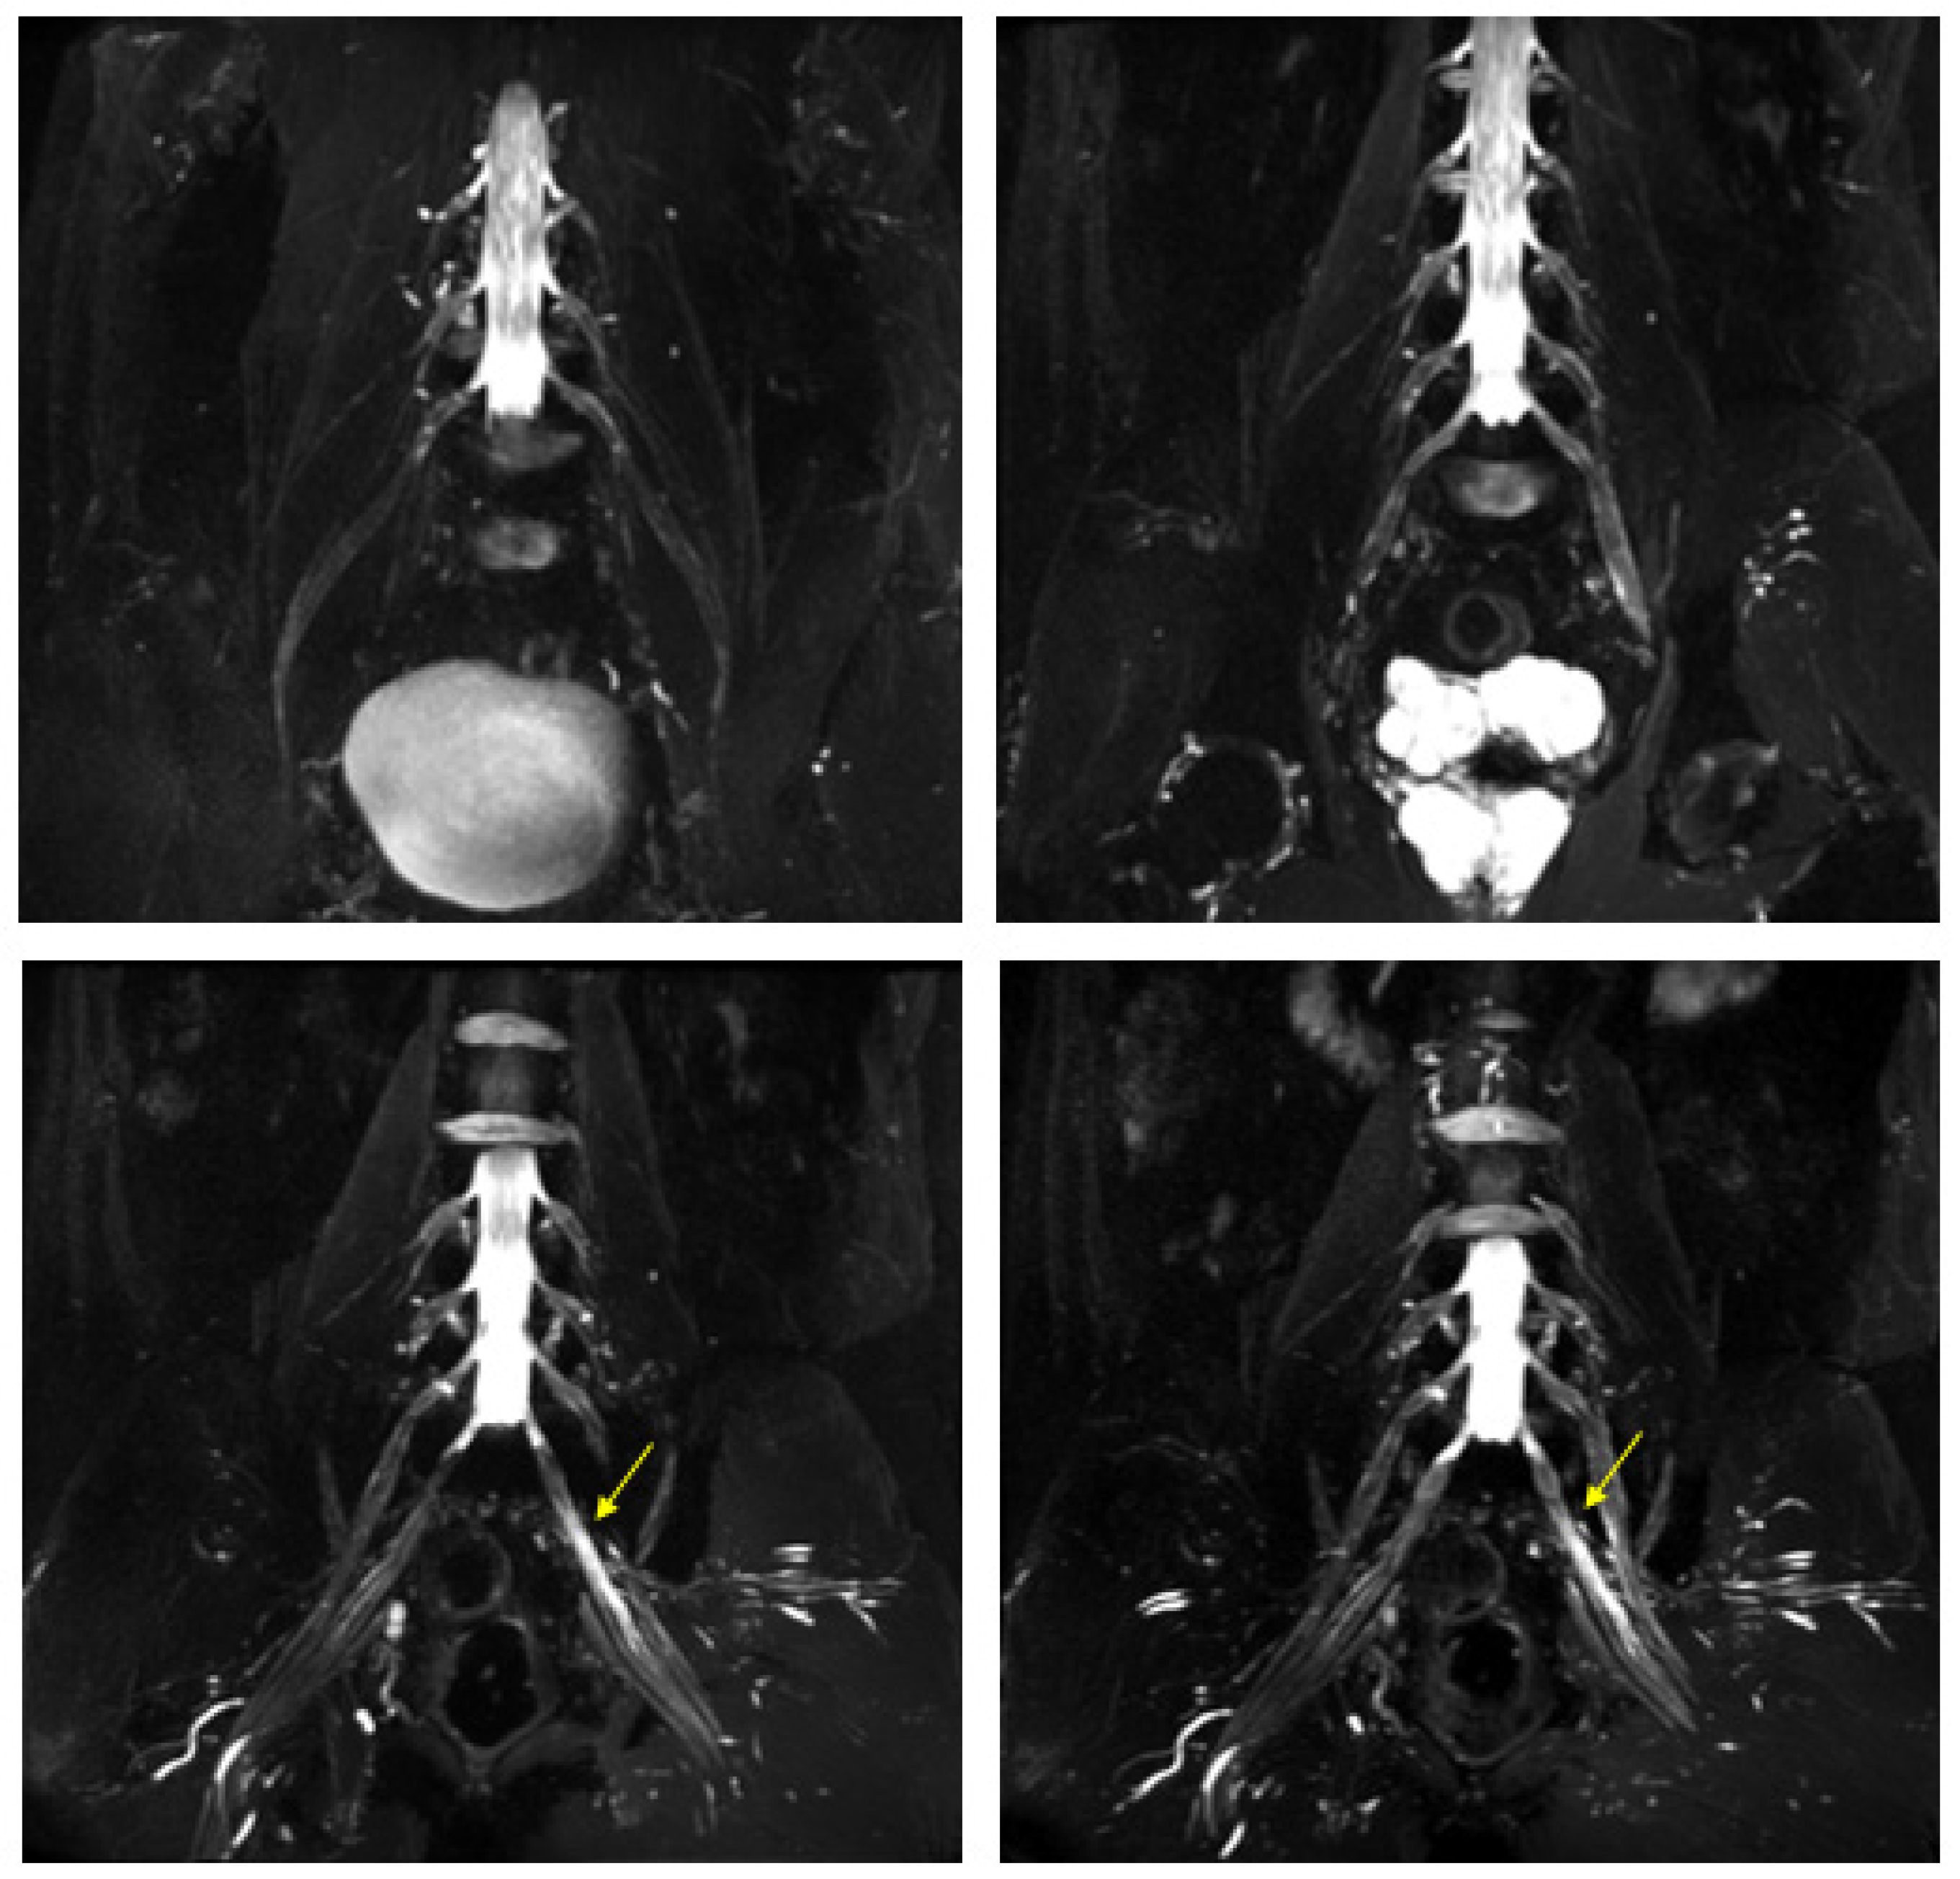

Figure 3.

MIP (Maximum Intensity Projection) reconstructions of the 3D cube nerve MR sequence of the brachial (A) and lumbosacral (B) plexus showing a pathological and asymmetric thickening and increase in T2 signal representation of them.

Figure 4.

MR 3D cube nerve images show thickening and T2 hyperintensity of the left obturator nerve (thin arrow in A) and lumbosacral trunk (thick arrow in B) compared to the contralateral one (transverse diameter on left L5 root 7.7 mm (n.v. * 5.99 ± 0.66) and on left S1 root 9.1 mm (n.v. * 5.27 ± 0.53). * Normal values (n.v.) according to the recent study of Su X et al. [20].

Figure 5.

MR 3D cube nerve images show thickening and T2 hyperintensity of brachial plexus and in particular in (A), we can observe a pathologic left C6 root (thin arrow transverse diameter of C6 left root 10.3 mm; n.v. * 4.57 ± 0.51); in B, we can observe the involvement of left trunks and cords (arrowheads) and in (B,C), we can observe the involvement of the peripheral nerves of the bilateral arms (thick arrows). * Normal values (n.v.) according to the recent study of Su X et al. [20].